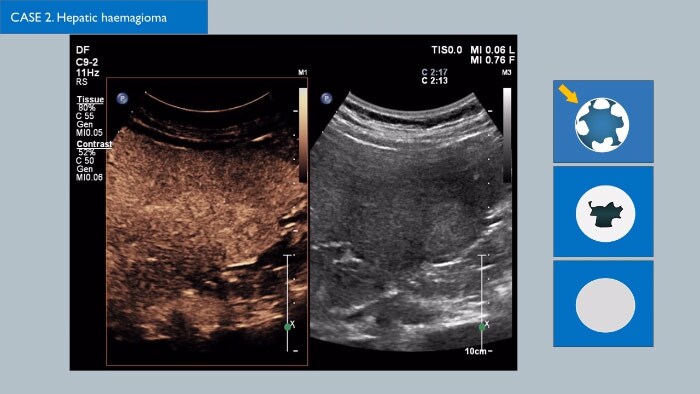

- Lesion Characterization: contrast-enhanced ultrasound plays a role in the differentiation between benign and malignant focal liver lesions. This differentiation relies on the observation or processing of the dynamic vascular pattern in a lesion with respect to its surrounding tissue parenchyma.